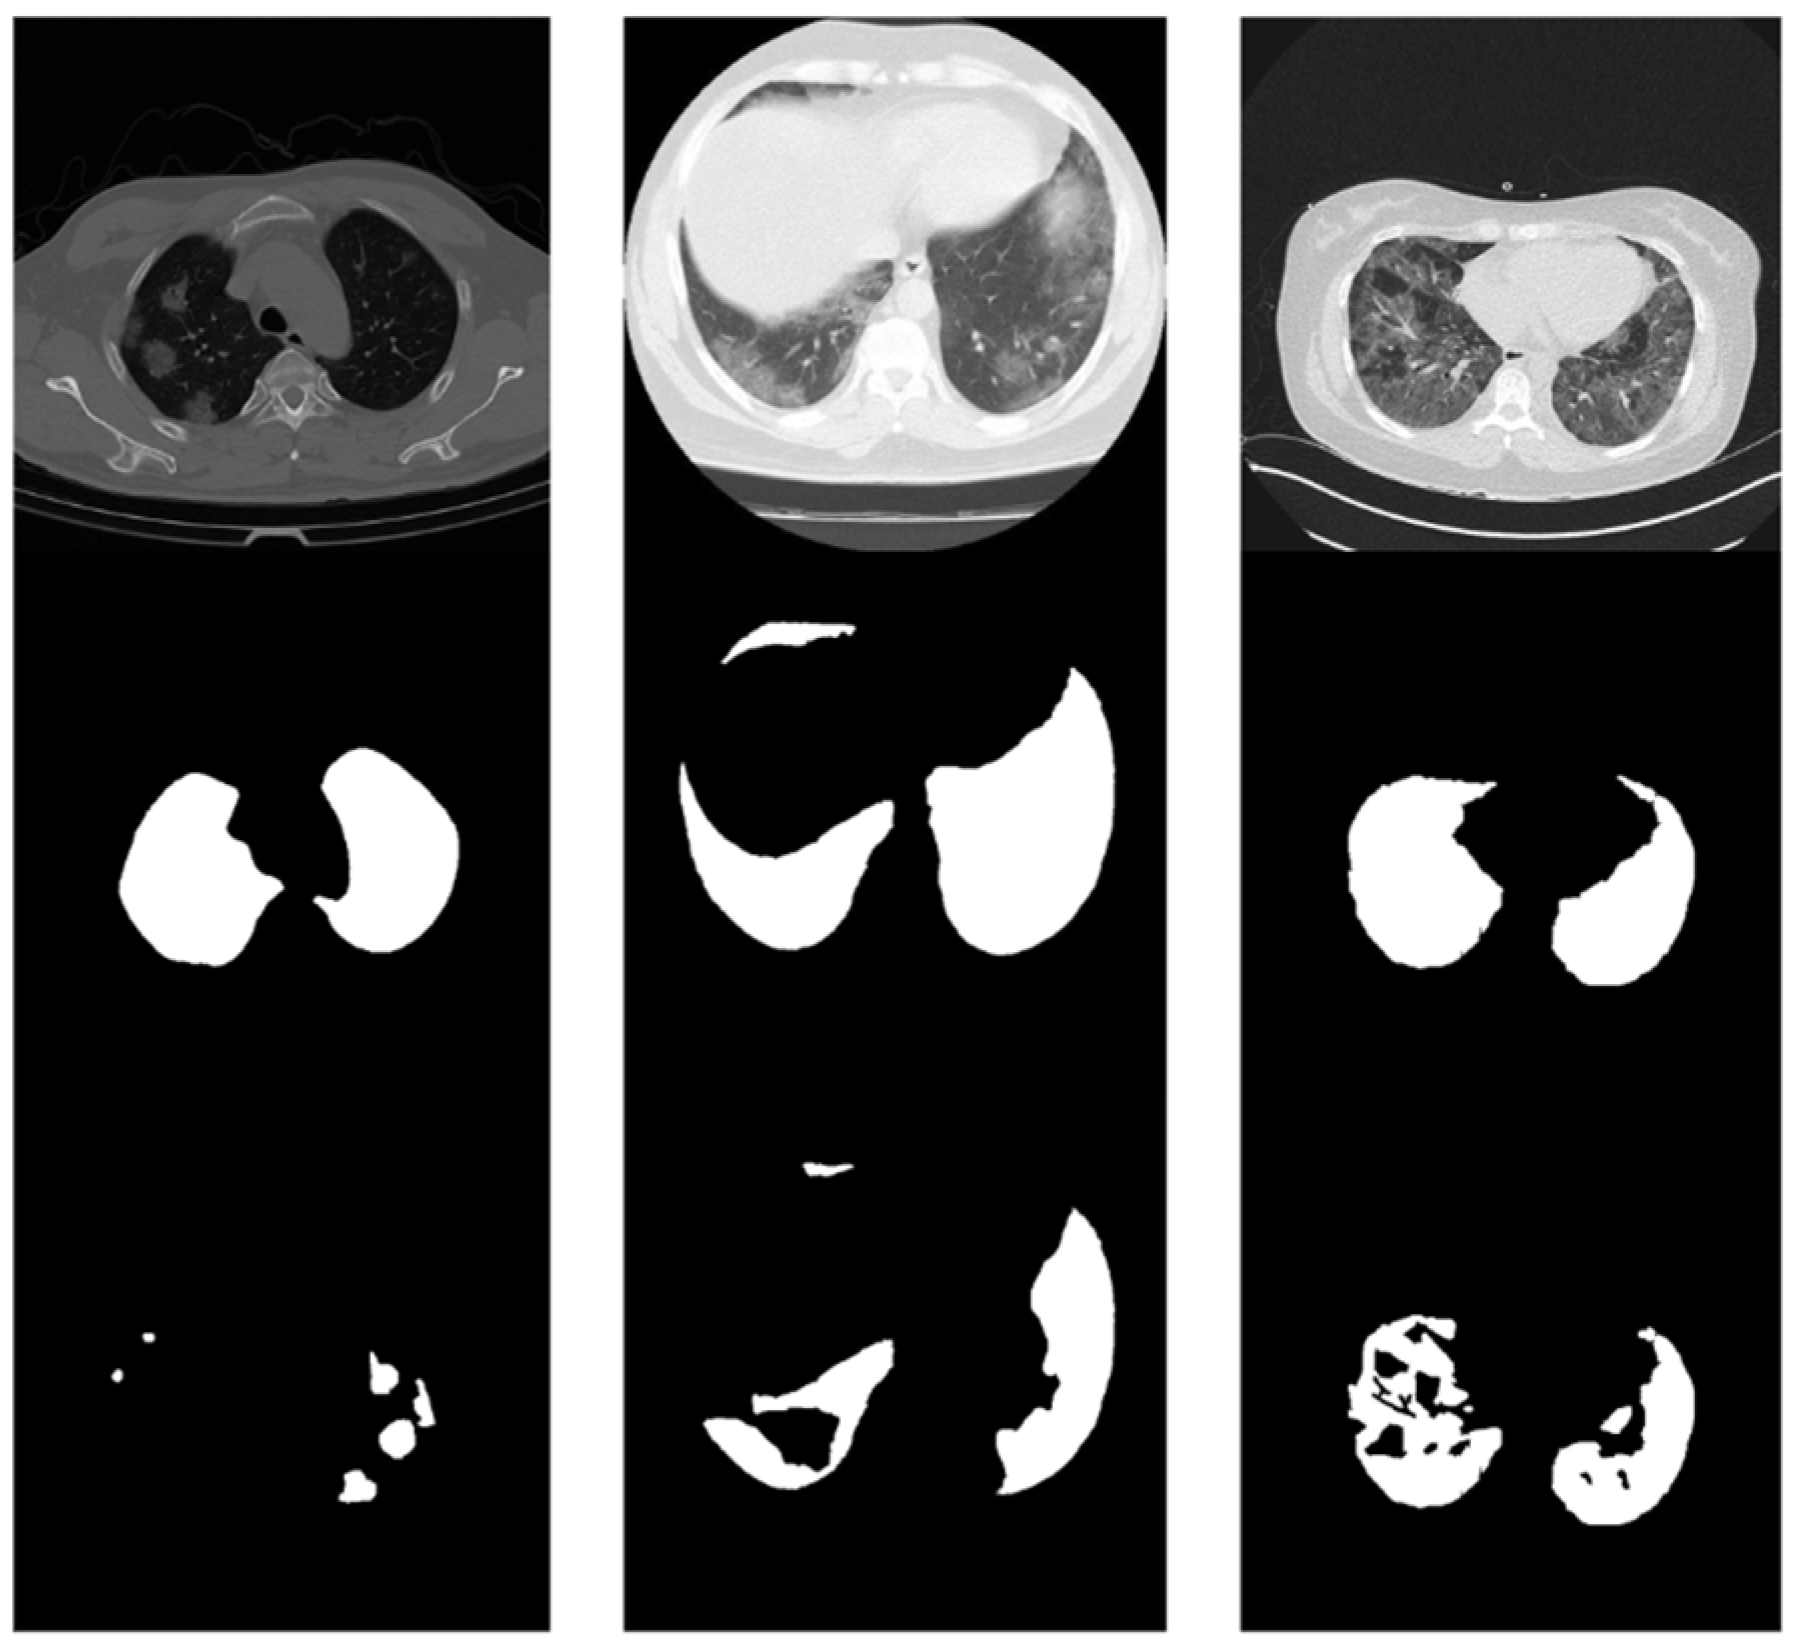

3.1. Lung Segmentation Results

3.5. Lung and COVID-19 Segmentation Examples